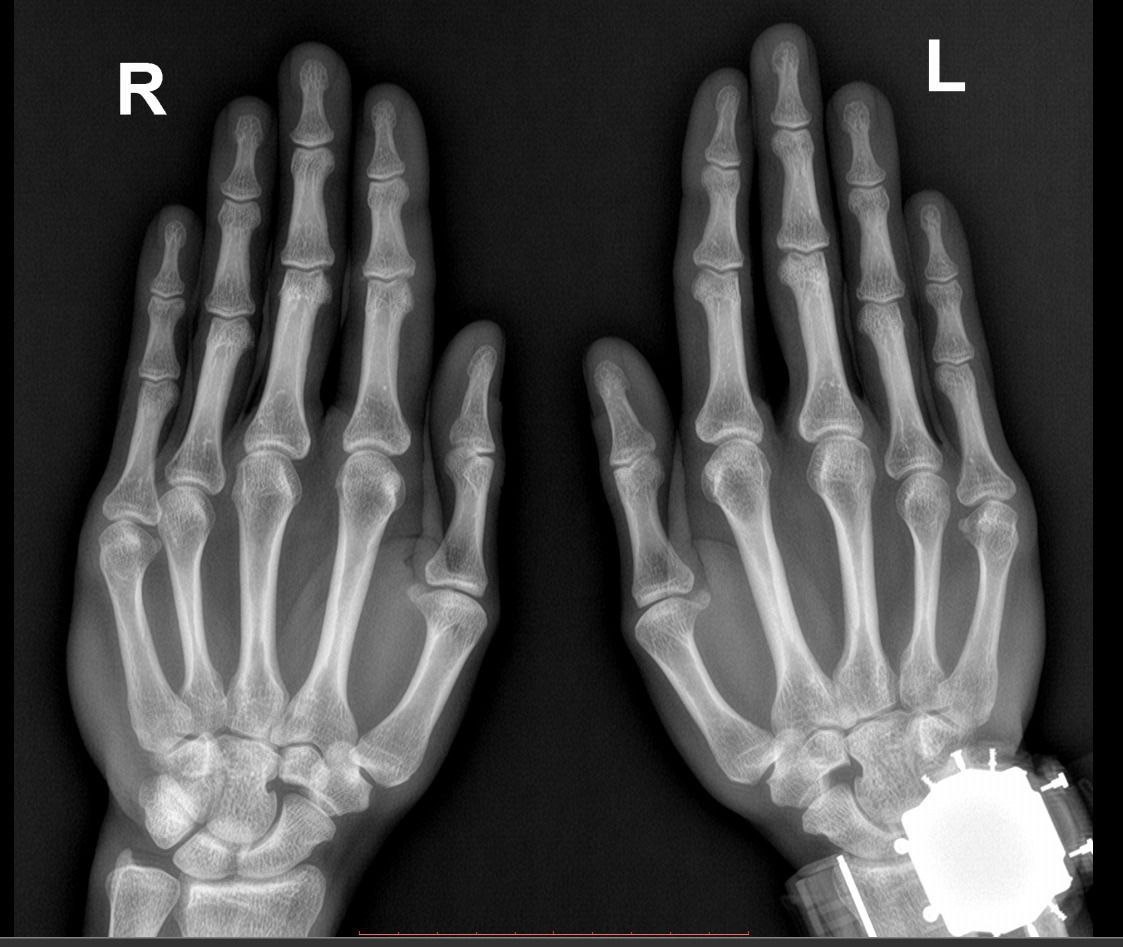

Как выглядит снимок перелома внутренней стороны второй фаланги соударением? Перелом второго пальца правой руки

Рентгенограмма кисти. Как выглядит снимок перелома внутренней стороны второй фаланги соударением? Перелом второго пальца правой руки